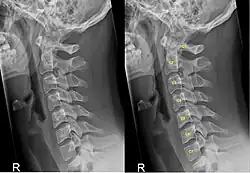

Röntgenfoto in zijwaartse richting van de cervicale wervelkolom. Links zonder, rechts met annotatie.